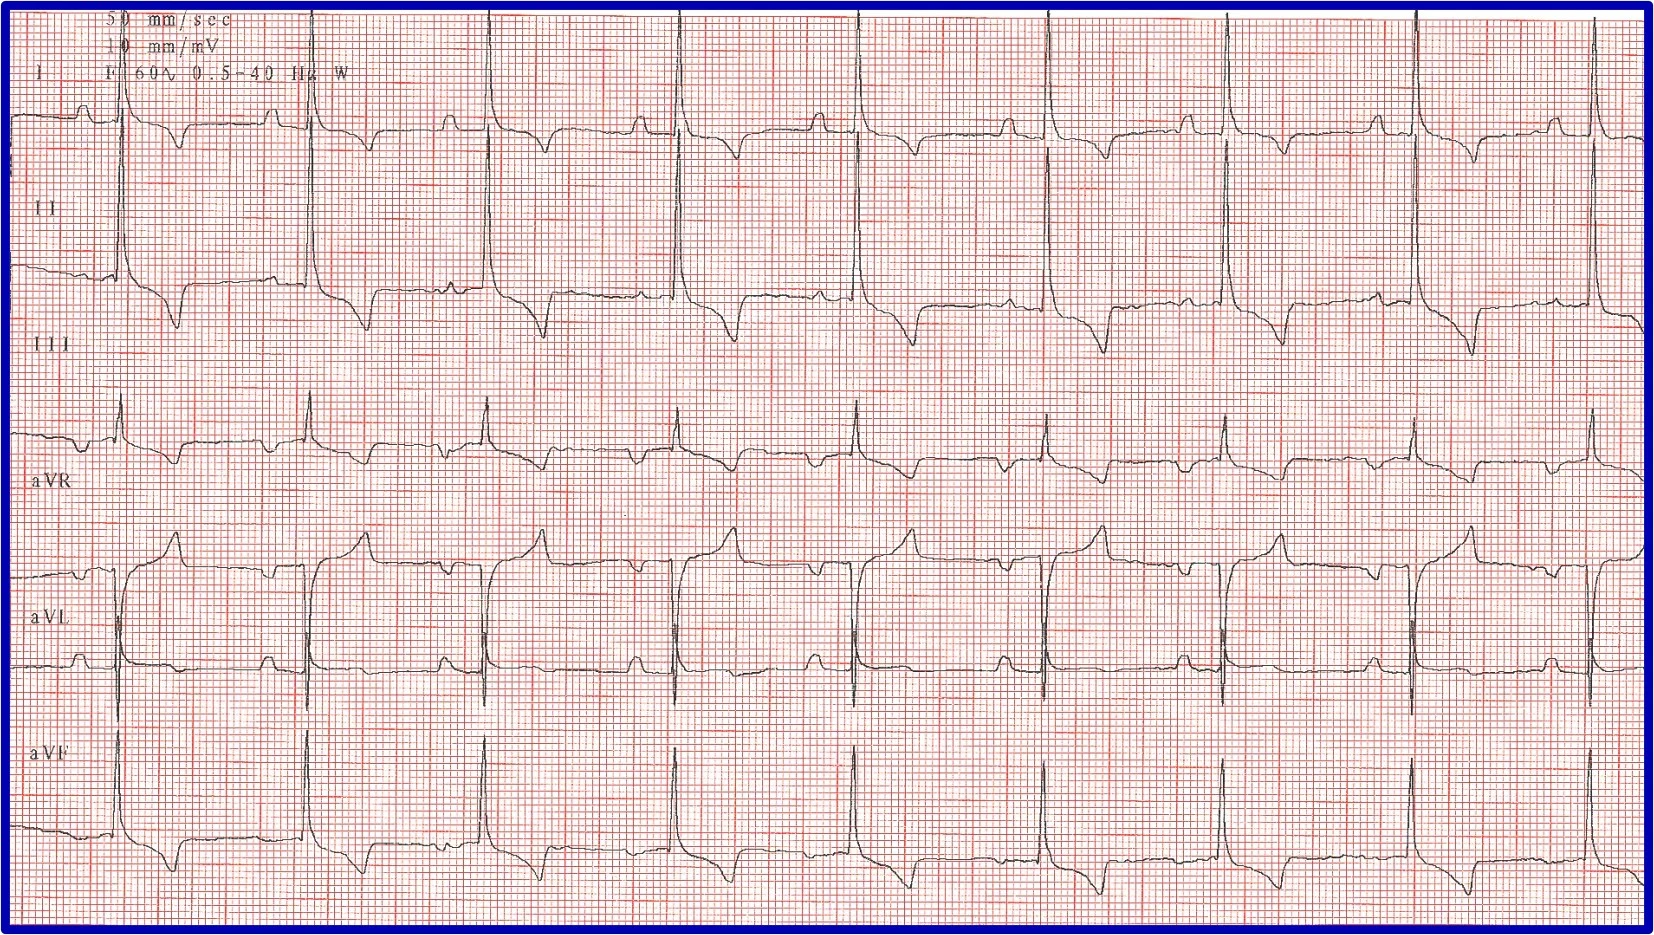

Heart rate in a normal or expected range for the breed, species, and clinical situation (eg, sinus arrhythmia and/or wandering pacemaker are considered normal in a relaxed dog but are not normal in a cat being examined in a clinical setting; Figures 1-3)

ECG showing a normal sinus rhythm

ECG showing a sinus arrhythmia with a regularly irregular rhythm, in which the heart rate increases and decreases in a pattern. This is considered normal in relaxed dogs.

ECG and illustrations showing a wandering pacemaker. Tall P waves with fast heart rates and high sympathetic tone and short P waves with slow heart rates and high vagal tone can be seen. This is considered normal in relaxed dogs.